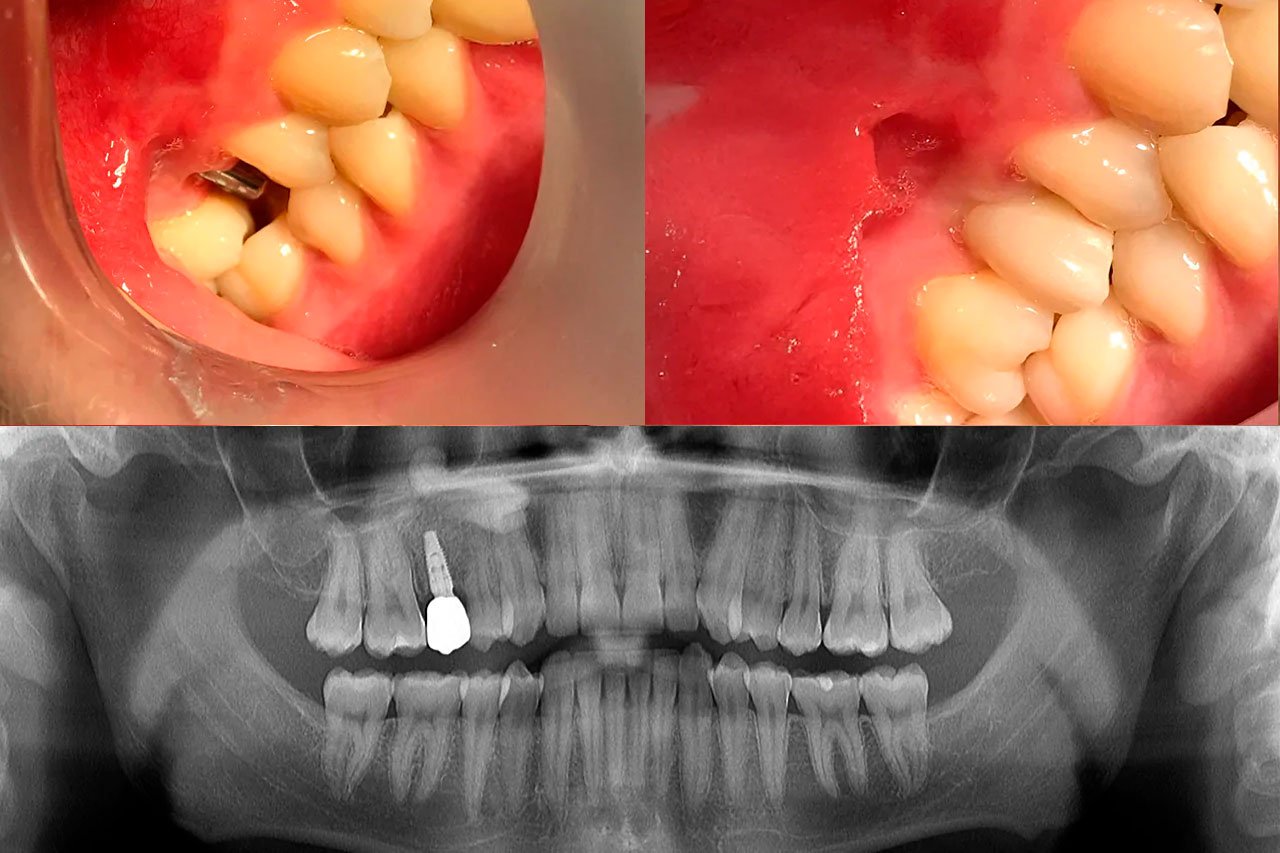

Um implante de carga imediata unitária é um procedimento em que um implante dentário é colocado na boca e, ao mesmo tempo, recebe uma prótese provisória, permitindo que o paciente tenha dentes funcionais logo após a cirurgia. Essa técnica é bastante utilizada para preservar a estética e a funcionalidade, além de reduzir o tempo total do tratamento. Após o tempo biológico se coloca a coroa definitiva sobre implante.

- Quando o paciente fratura ou quebra o dente, que não da mais para aproveitar, fazemos um implante imediatamente e coloca um dente provisório

Quando o paciente fratura a raiz ou quebra o dente, que não da mais para aproveitar, indicamos remoção e implante.